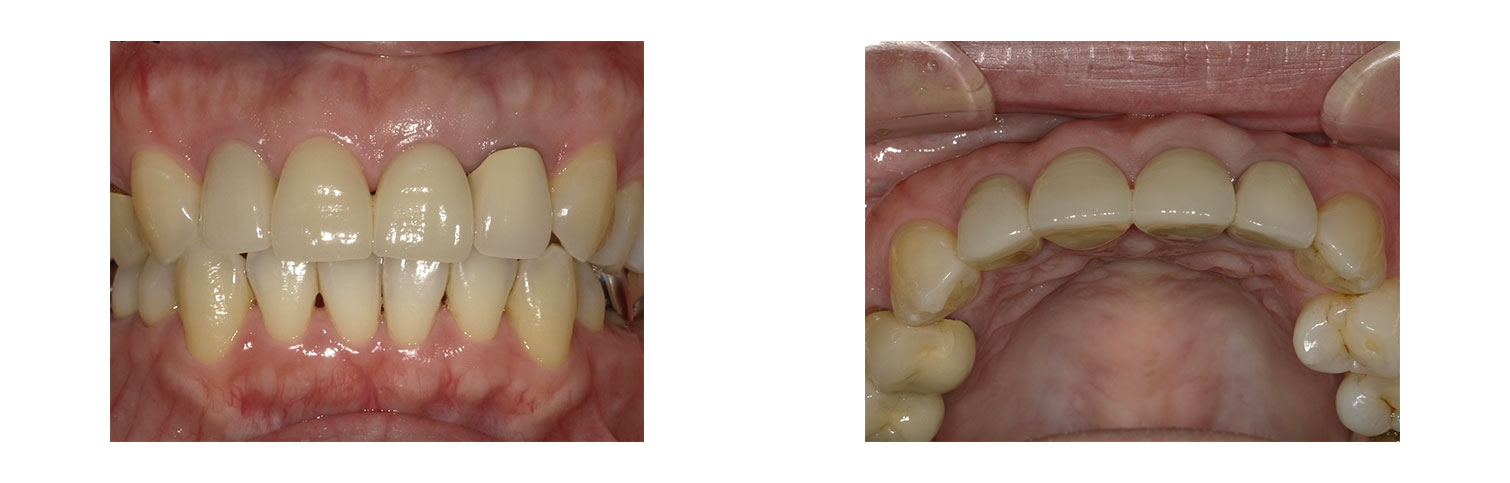

左上1番 抜歯即時インプラント(ルートメンブレンテクニック併用)

BEFORE

AFTER

ルートメンブレンテクニックの併用により、唇側歯肉の豊隆が保持されます。

| 金額 | ¥590,000(税抜) |

| 期間 | 約6ヶ月 |

| リスク | オペから6週までは過大な力がかかると骨の2次安定が得られないことがあるため、注意を要する。 |